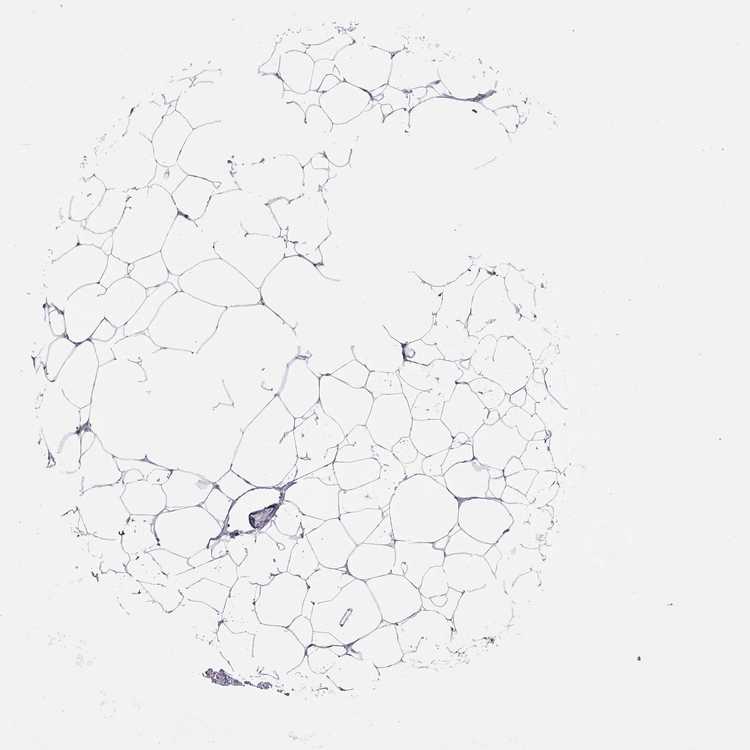

BREAST - Antibody stainingi

Antibody staining in the annotated cell types in the current human tissue is reported as not detected, low, medium, or high, based on conventional immunohistochemistry profiling in selected tissues. This score is based on the combination of the staining intensity and fraction of stained cells.

Each image is clickable and will lead to virtual microscopy that enables deeper exploration of all samples and also displays staining intensity scores, fraction scores and subcellular localization as well as patient and tissue information for each sample.

Antibody HPA077312

Adipocytes Not detected

Glandular cells Not detected

Myoepithelial cells Not detected